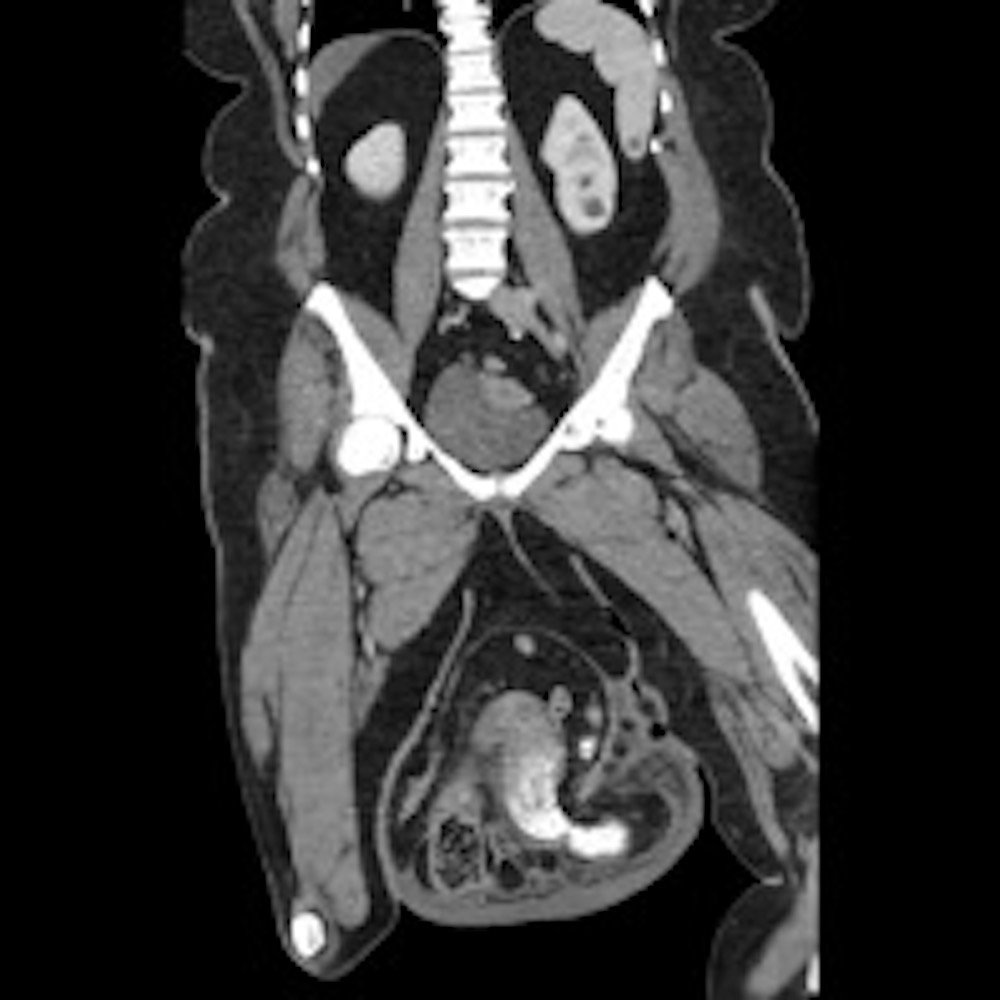

Computed tomography (CT) scan with intravenous (IV) contrast of the abdomen and pelvis demonstrated a large pannus containing a ventral hernia with abdominal contents extending below the knees (white circle), elongation of mesenteric vessels to accommodate abdominal contents outside of the abdomen (white arrow) and air fluid levels (white arrow) indicating a small bowel obstruction.